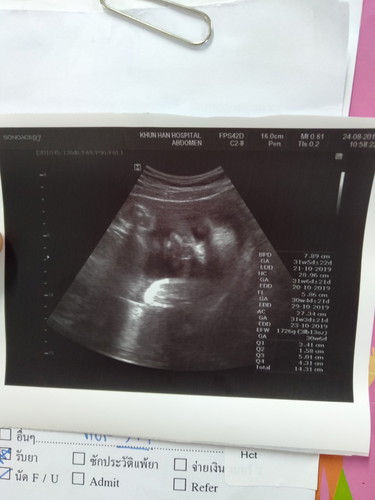

ท้องแรก32w

31+2d ตื่นเต้นเหมือนกันค่ะ คิดถึงวันที่ตรวจเจอ2ขีดสีแดงยังคิดว่าเป็นเมื่อวานอยู่เลยค่ะเวลาผ่านไปไวมาก พอใกล้คลอดก็รู้สึกเวลาเดินช้าจัง😊

ใช่เลยค่า ตอนนี้ 32 วีคเท่ากันเลย รู้สึกวันเวลาเดินช้ามากกกก... เพราะเรารอคอยเค้า อยากให้ถึงกำหนดวันคลอดเร็ว ๆ ☺️☺️

31w6d อยากเจอแล้วเหมือนกันค่ะงดใจรอไม่ไหวแล้วคนแปลกหน้าที่อยากเจอมากที่สุด🥰

32เช่นกันค่ะ ช่วงนี้ท้องแข็งบ่อย กรดไหลย้อน หลับยากเหลือเกินค่ะ

บ้านนี้36วีคกว่าแล้ว เฝ้ารอเจอหน้าตัวเล็กทุกวันค่ะ💙